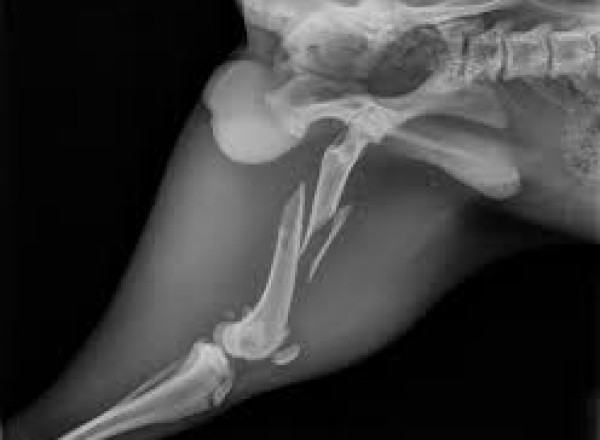

L'IMAGERIE : RADIOGRAPHIE, ECHOGRAPHIE et FIBROSCOPIE

La clinique dispose de matériels très performants qui participent au diagnostic, au dépistage et au suivi de très nombreuses pathologies.Ils servent également au diagnostic de gestation et au suivi optimal des chatons et des chiots.

La salle radio est entièrement plombée et possède une développeuse automatique garante de qualité.L'échographie et la fibroscopie sont assurées par des appareils très efficaces (General Electric et Fujinon).